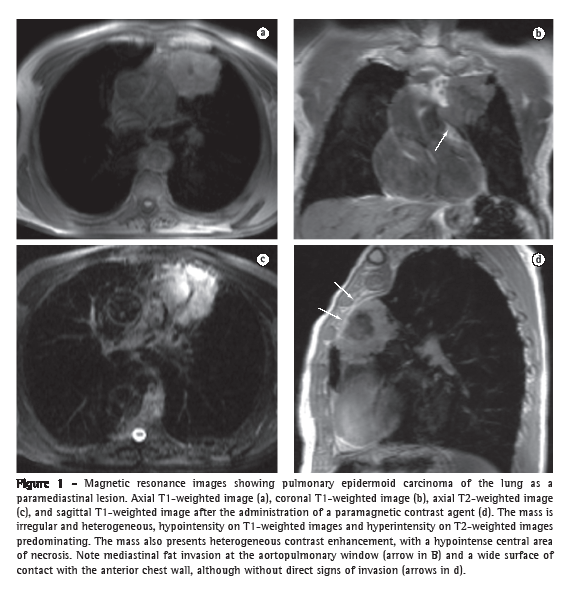

In general, bronchogenic carcinoma appears on MRI as a solid, irregular lesion, ranging from hypointense to isointense on T1-weighted images and hyperintense on T2-weighted images, with intense enhancement after the administration of contrast material, being heterogeneous in larger lesions due to areas of central necrosis. Even in lesions outside the superior sulcus, MRI can better identify direct invasion of adjacent structures (Figure 1), including the mediastinum (aortopulmonary window and remaining spaces), trachea, bronchi, chest wall, diaphragm (costophrenic angle tumor and cardiophrenic angle tumor), heart (pericardium or myocardium), and large blood vessels (aorta and pulmonary arteries). The sensitivity of MRI in differentiating between T3 and T4 tumors is similar to that of CT. However, MRI is more accurate in identifying mediastinal and hilar invasion. The use of dynamic cine MRI can increase MRI specificity in detecting invasion of the chest wall and pericardium. New MRI techniques have increased the sensitivity of the test in detecting mediastinal lymph nodes that are suspected of being metastatic. A short inversion time (TI) inversion recovery sequence (a T2-weighted technique with fat suppression by inversion and recovery) allows the differentiation between metastatic and non-metastatic lymph nodes in patients with non-small cell tumors, metastatic lymph nodes being more intense.(12-15)